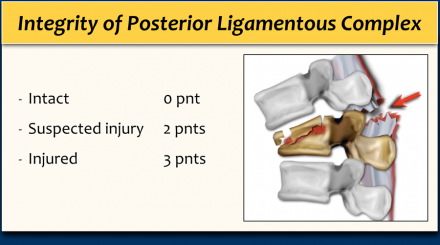

CT features of PLC pathology are:

- Widening of the interspinous space.

- Avulsion fractures or transverse fractures of spinous processes or articular facets.

- Widening or dislocation of facet joints.

- Vertebral body translation or rotation.

When the PLC is definitely injured on CT, it can already be scored as 3.

Since the integrity of the PLC depends mostly on ligamentous structures, MR is sometimes needed to adequately diagnose pathology of the PLC, especially when there is no dislocation or disruption on CT.

MRI features of PLC pathology are:

- Definite: 3 points

- Loss of normal low signal intensity of the ligamenta flava or supraspinous ligaments on T1 and T2.

- Indeterminate: 2 points

- Edema without clear rupture; high signal intensity of the interspinous ligaments or along the facet joints on T2 SPIR or STIR.

MRI has a tendency to overdiagnose PLC injury (4).